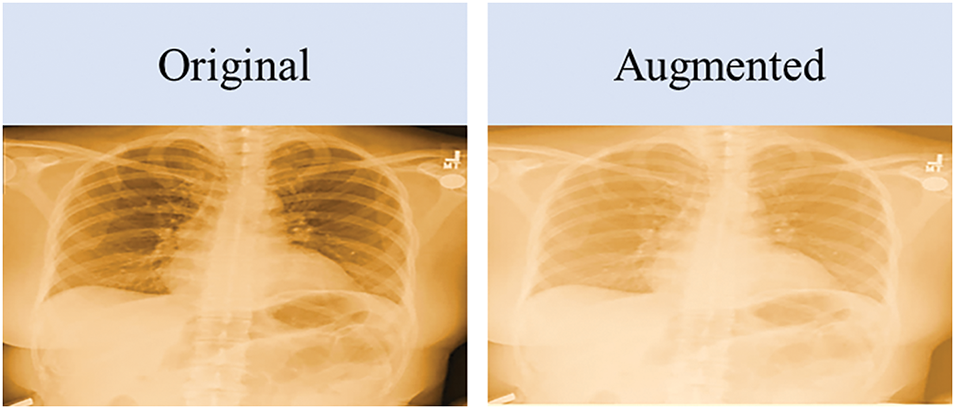

The NIH dataset available on Kaggle only includes 189 X-ray images, which were not sufficient to detect the adduced disease. To overcome this limitation, we employed a data augmentation technique. The proposed approach applies data augmentation to the training dataset after the training/testing split to achieve two primary goals: balancing the classes in the dataset and enhancing the dataset for better modeling. The data augmentation process is explained in Algorithm 1. Ensuring an abundance of data is vital for high-quality results, enabling the productive deployment of most DL models. Data augmentation is a method to artificially enhance data from existing data. Fig. 4 shows the original image vs. images generated using the data augmentation technique. An augmented image retains the same features and intensity as the original image.

Figure 4: Original image vs. augmented image